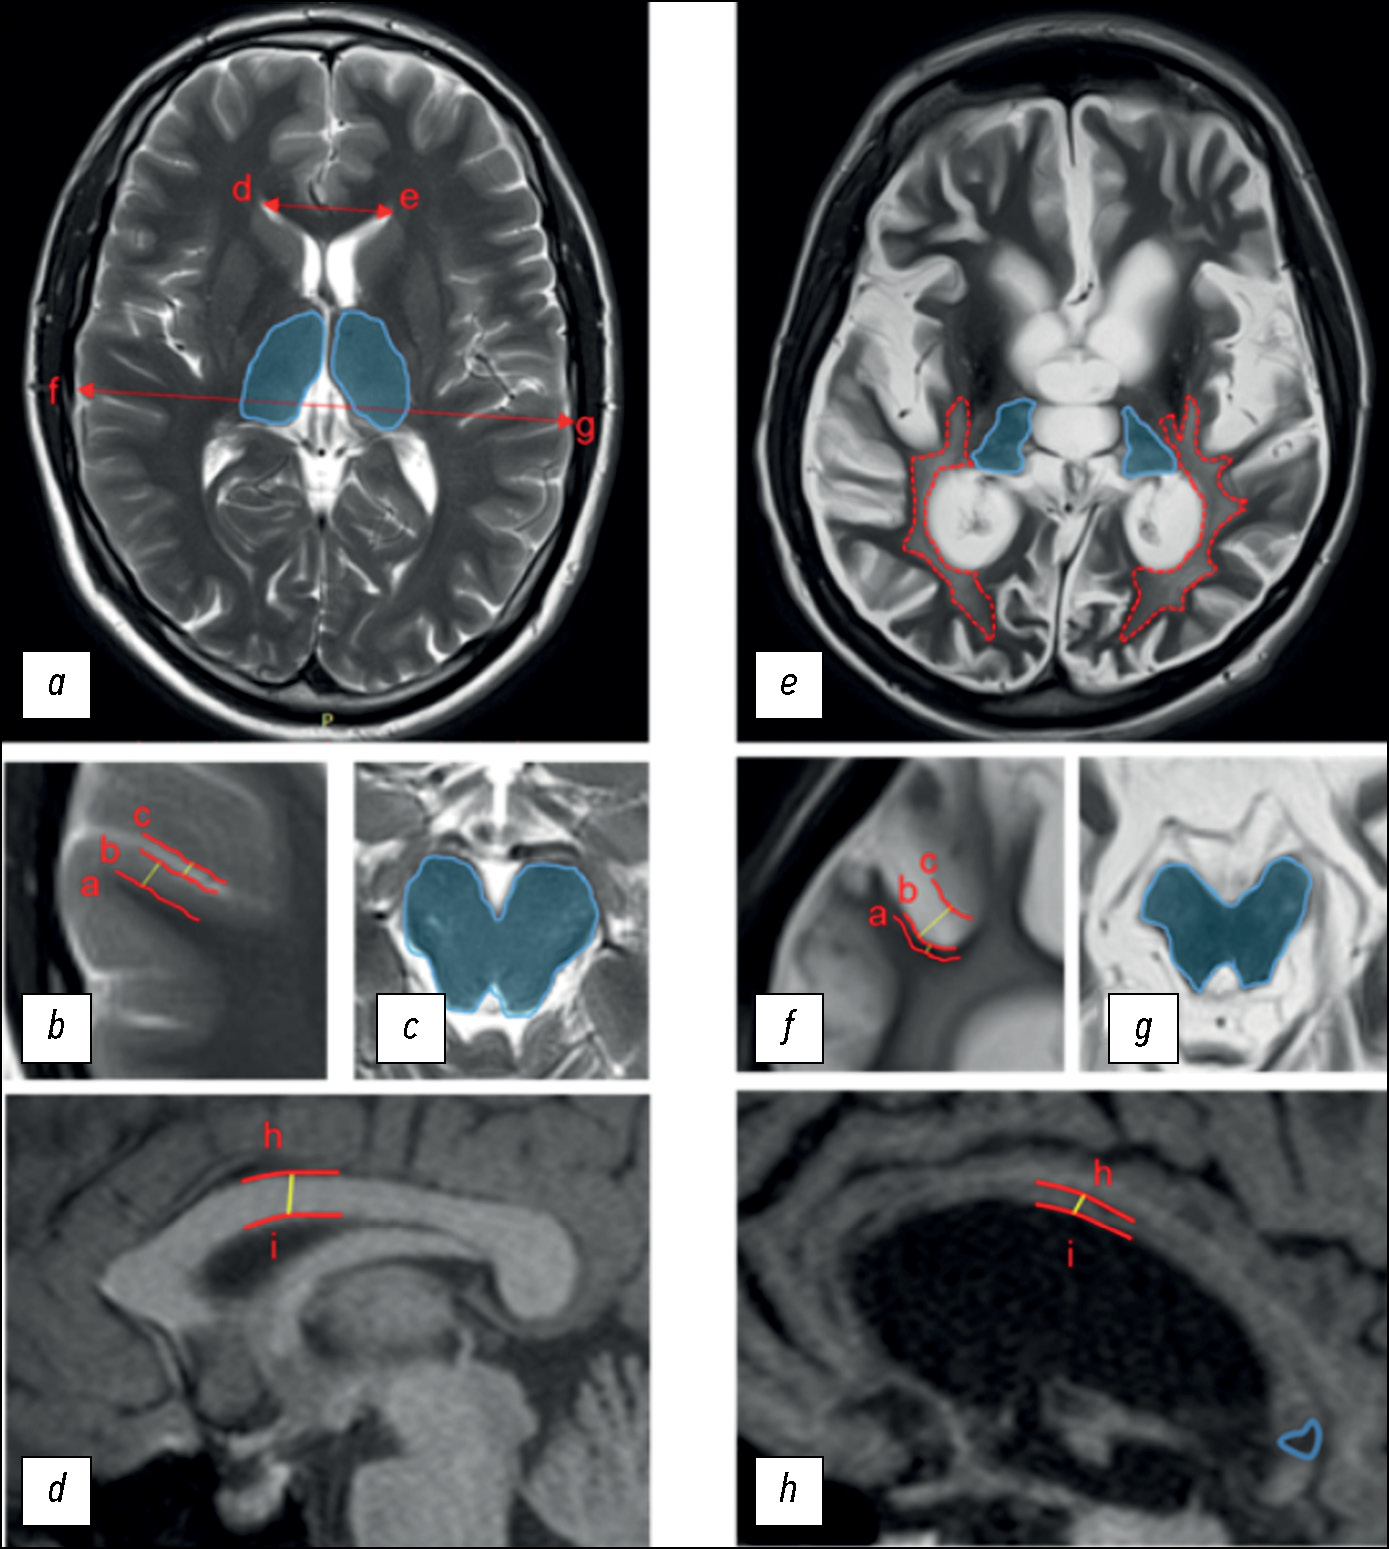

Conventional structural magnetic resonance imaging in differentiating chronic disorders of consciousness

Abstract

BACKGROUND: Differential diagnosis of chronic disorders of consciousness remains one of the most difficult problems even for experienced clinicians.

AIM: To evaluate the inter-expert consistency and capacity of the researcher-developed structural scale based on magnetic resonance imaging to differentiate chronic disorders of consciousness, named, DOC-MRIDS, on a larger sample of patients.

MATERIALS AND METHODS: Sixty patients with a clinically stable status diagnosed with consciousness disorders (vegetative state, n=32; minimally conscious state, n=28) were enrolled. The revised coma recovery scale (CRS-R) was included in the clinical assessment. All patients underwent structural magnetic resonance imaging with 3.0-T Siemens scanners including T2 and T1 sequences. Structural changes were assessed using the DOC-MRIDS scale and included the following features: diffuse cortical atrophy, ventricular enlargement, gyri dilatation, leukoaraiosis, brainstem and/or thalamic degeneration, corpus callosum degeneration, and focal corpus callosum lesions. A total score was calculated. Magnetic resonance imaging data were analyzed by three neuroradiologists, and inter-observer agreement (Krippendorf’s alpha) was assessed.

RESULTS: A high inter-examiner agreement of the DOC-MRIDS scale score was found, with α=0.806 (95% confidence interval 0.757–0.849). The vegetative state group had a higher DOC-MRIDS score than the minimally conscious state group (p <0.005). A negative correlation was obtained between CRS-R and DOC-MRIDS scale scores (ρ=–0.457, p <0.0001), individual clinical scale domains, and magnetic resonance imaging features.

CONCLUSION: When assessing structural changes in patients with chronic consciousness disorders, the use of the DOC-MRIDS scale helps differentiate the type of such disorders with sufficient specificity, sensitivity, and inter-rater agreement. This scale can be used in clinical practice as an additional differential diagnostic tool.

190-202